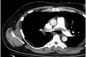

The Pulmonary Embolism Response Team (PERT) is made up of specialists from Critical Care Medicine, Interventional Radiology, and Thrombosis. The purpose is to provide physicians and their patients rapid access to a multidisciplinary team of experts in dealing with life-threatening pulmonary emboli